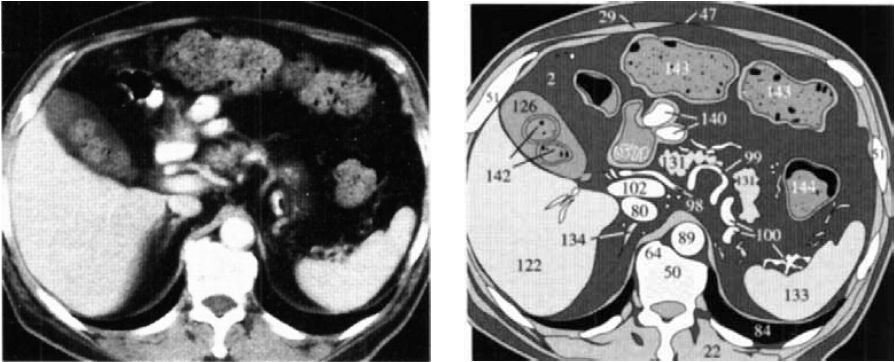

У некоторых людей край правой

доли печени (122) выглядит фестончатым из-за вдавлений диафрагмы (30), которые

не следует принимать за патологические образования печени (фото 1). Стенки

незаполненного желудка (129) толстые и напоминают злокачественное

новообразование (129а).

Фото 1.